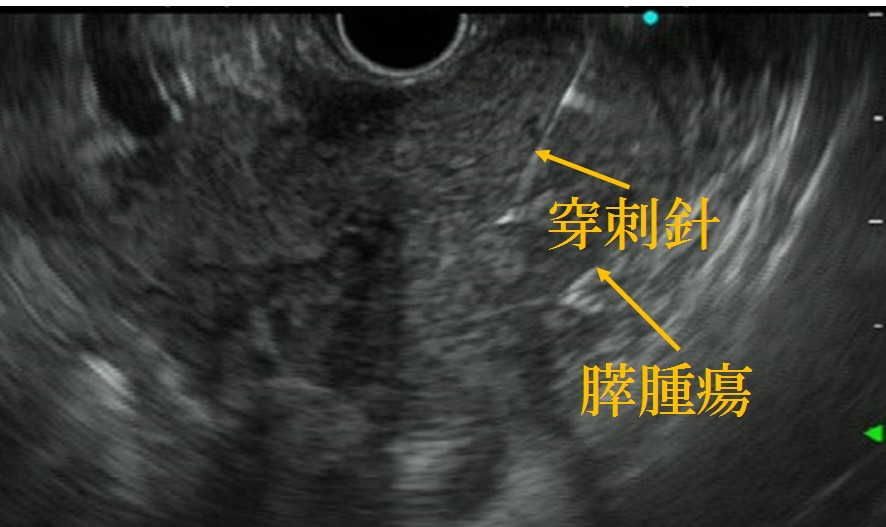

各種画像検査で診断を行います。必要に応じて、超音波内視鏡下穿刺吸引法(EUS-FNA)も施行しております(図4)。

図4 膵腫瘍に対する超音波内視鏡下穿刺吸引法(EUS-FNA)。